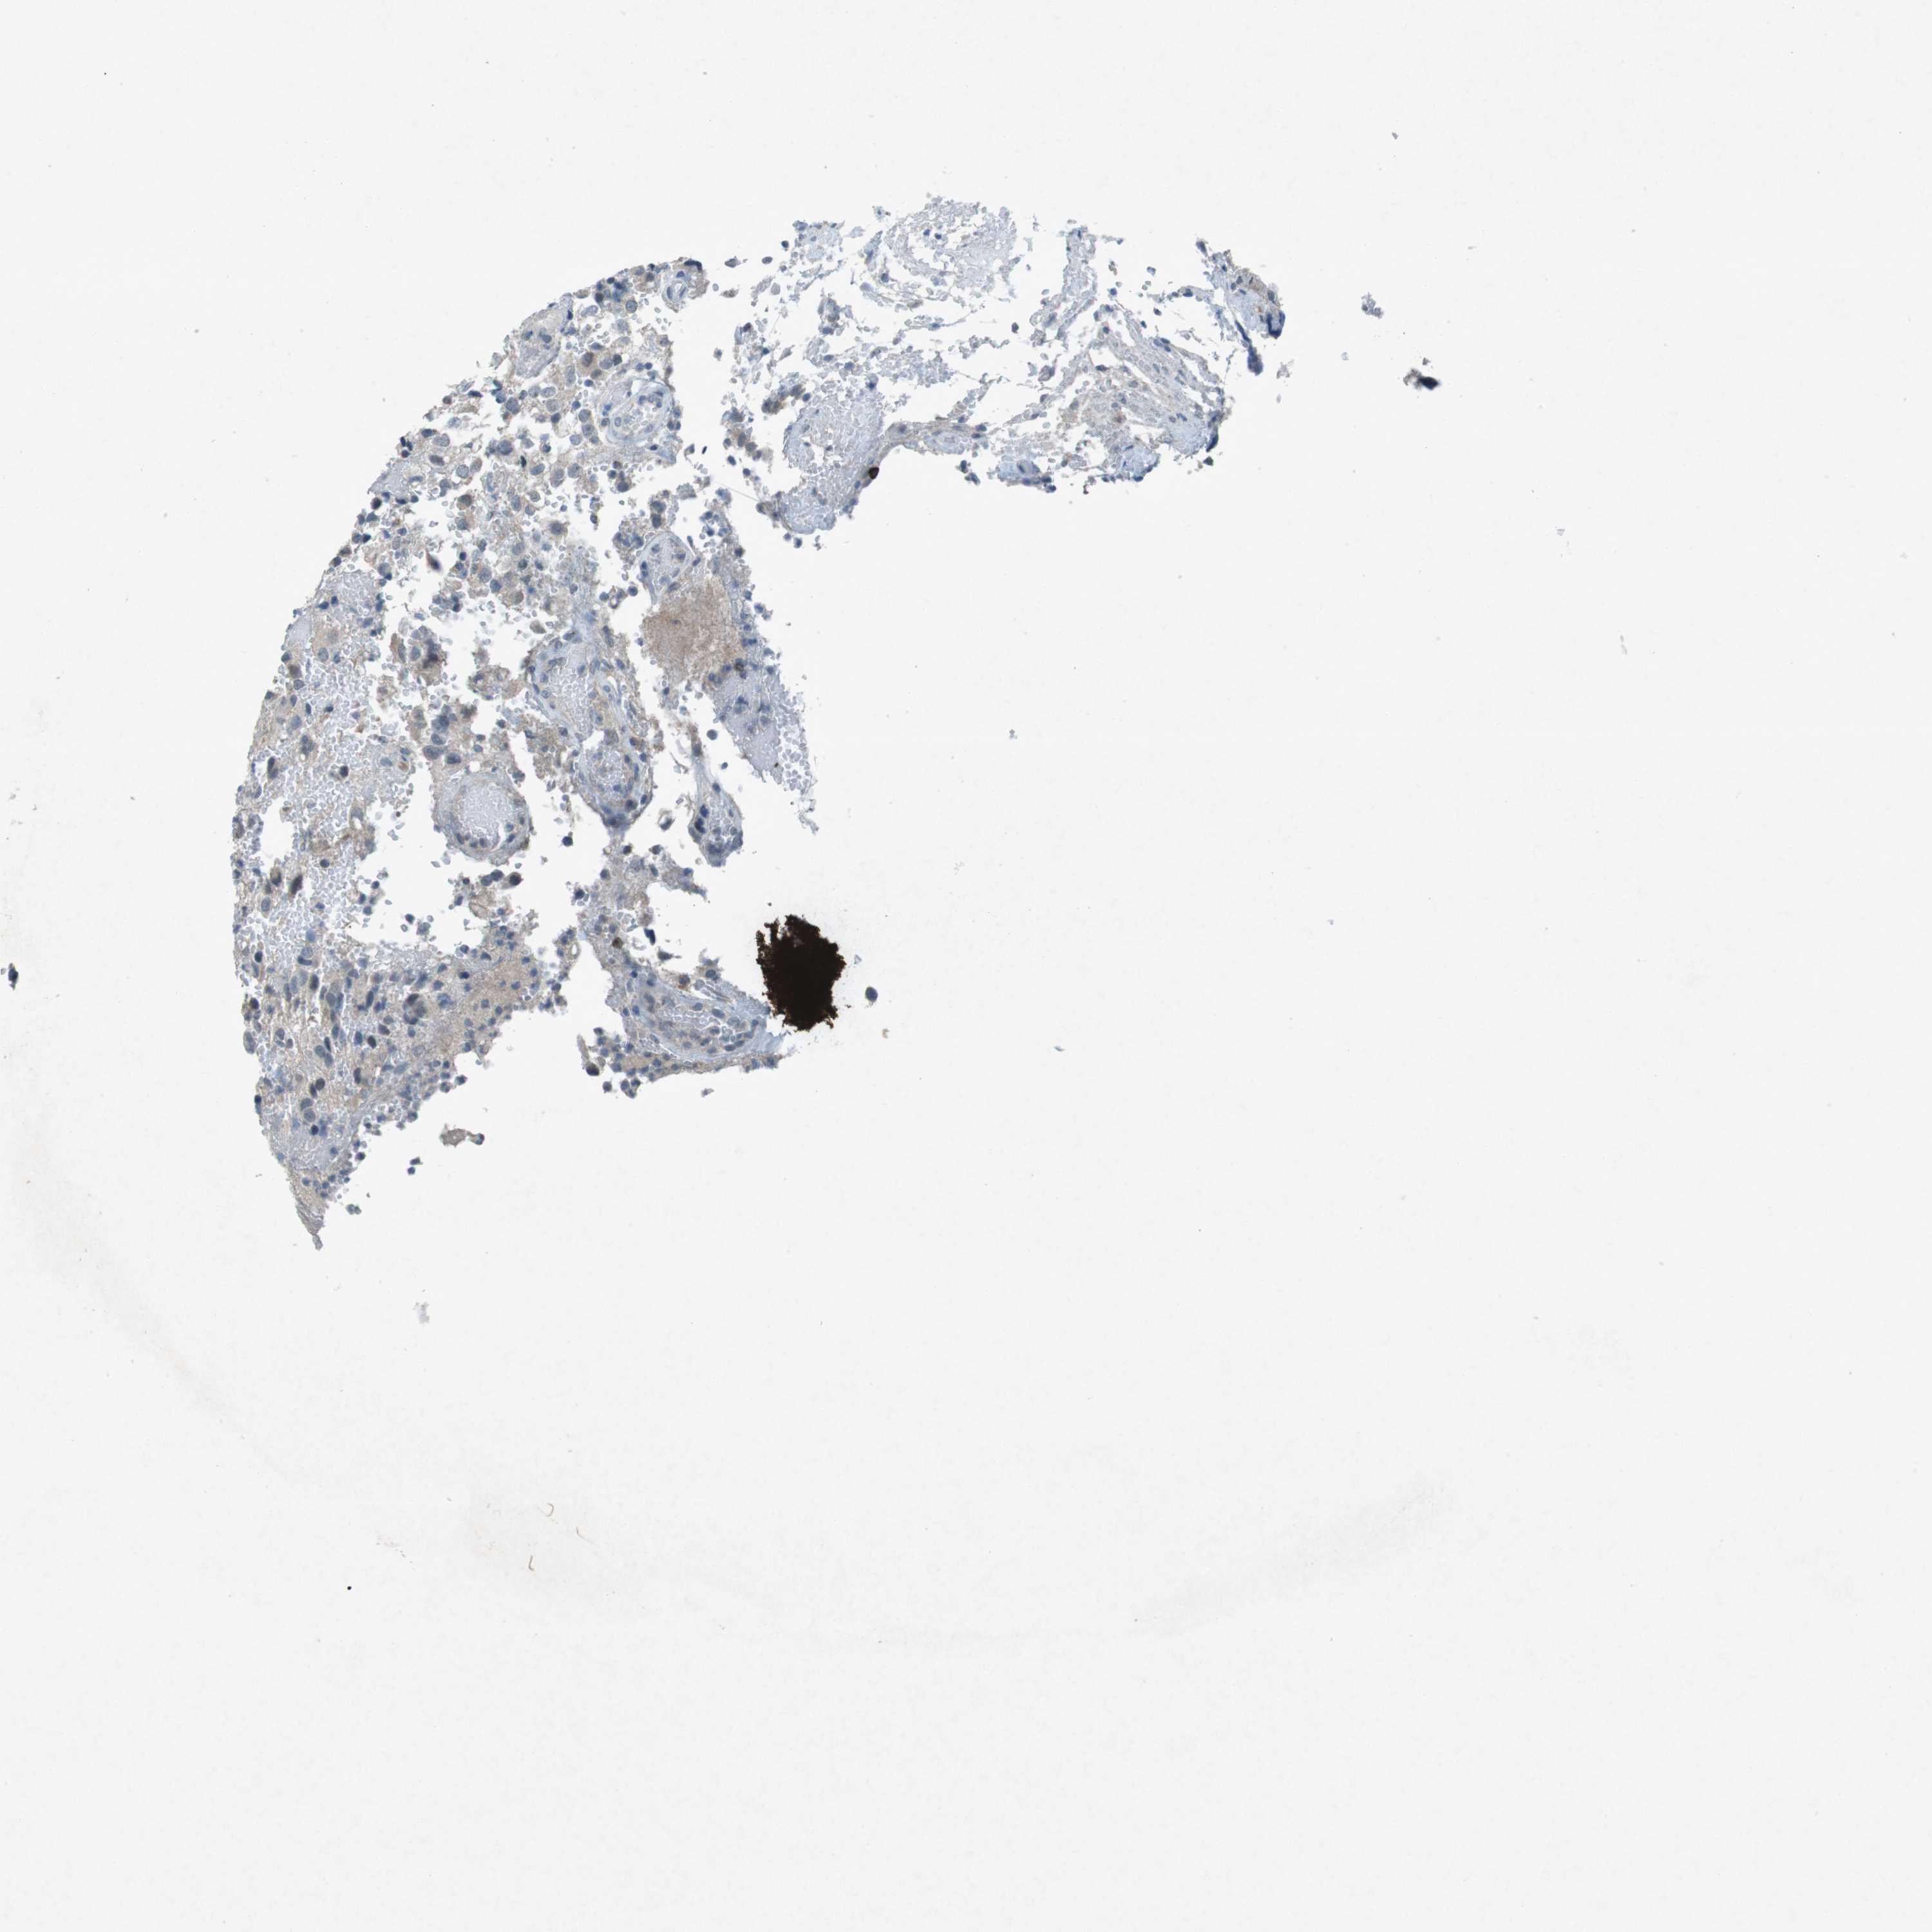

GLIOMA - Protein expressioni

A mouse-over function shows sample information and annotation data. Click on an image to view it in a full screen mode. Samples can be filtered based on level of antibody staining by selecting one or several of the following categories: high, medium, low and not detected. The assay and annotation is described here.

Note that samples used for immunohistochemistry by the Human Protein Atlas do not correspond to samples in the TCGA dataset.

Antibody stainingi

Antibody staining in the annotated cell types in the current human tissue is reported as not detected, low, medium, or high, based on conventional immunohistochemistry profiling in selected tissues. This score is based on the combination of the staining intensity and fraction of stained cells.

Each image is clickable and will lead to virtual microscopy that enables deeper exploration of all samples and also displays staining intensity scores, fraction scores and subcellular localization as well as patient and tissue information for each sample.

Antibody CAB016545

Staining

High

Medium

Low

Not detected

Intensity

Strong

Moderate

Weak

Negative

Quantity

>75%

75%-25%

<25%

None

Location

Nuclear

Cytoplasmic/membranous

Cytoplasmic/membranous,nuclear

Glioma, malignant, High grade

Glioma, malignant, Low grade